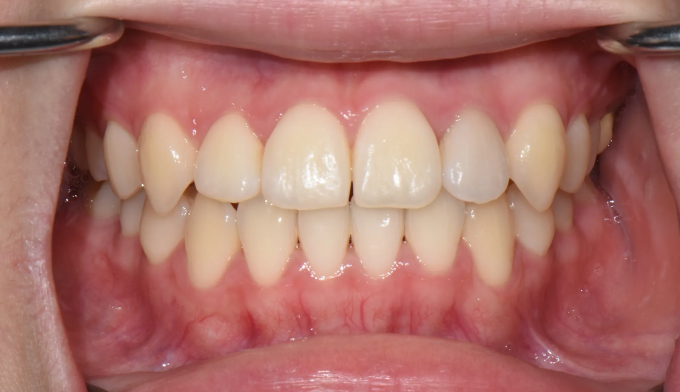

덧니가 심한 케이스 입니다. 발치를 하지 않고는 도저히 공간을 마련하기 힘들어 보입니다.

최대한 좁은 악궁을 확장하고 부족하면 전체 치열의 후방이동을 통하여 덧니를 배열할 공간을 만들었습니다.

총 치료기간은 25개월 입니다.

입술의 두께나 입매의 변화 없이 치열만 고르게 배열하였습니다.